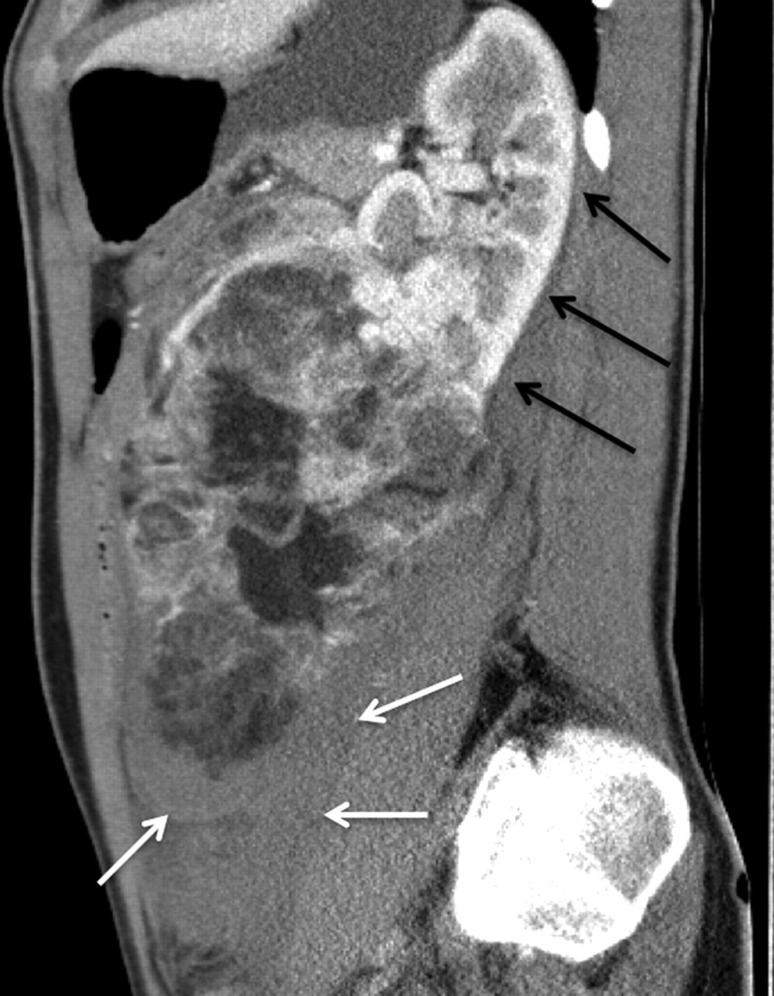

我们报告一位36岁的白人妇女,她以计算机断层扫描诊断为创伤后腹膜后出血而来到急诊室。患者临床稳定后,进行选择性动脉栓塞。血管平滑肌脂肪瘤的供血动脉用8毫米Amplatzer II型血管塞成功治疗。左肾上极由独立的肾上动脉供应,保存完好。结果,肾血管平滑肌脂肪瘤坏死,手术切除整个肾血管平滑肌脂肪瘤。本病例说明了一种简单有效的应用Amplatzer血管堵塞器进行血管栓塞,而无需额外缠绕。

We report on a 36-year-old Caucasian woman who presented to the emergency department with post-traumatic retroperitoneal bleeding diagnosed by computed tomography. After clinical stabilization of the patient, selective arterial embolization was performed. The angiomyolipoma's feeding artery was successfully treated with an 8-mm Amplatzer Vascular Plug Type II. The upper pole of the left kidney, which was supplied by a separate upper renal artery, was conserved. Consequently, the renal angiomyolipoma became necrotic and surgical resection of the entire renal angiomyolipoma was performed. This case illustrates a simple and effective application of an Amplatzer Vascular Plug occluder for vessel embolization, without additional coiling.